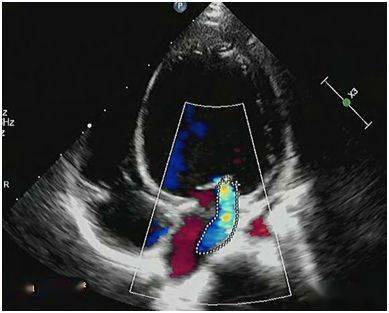

图2‐1‐194 组织多普勒成像正常人二尖瓣环水平组织频谱多普勒,em>am